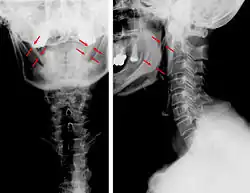

| Anteroposterior and lateral radiographs of cervical spine showing ossification of the stylohyoid ligament on both sides | |

CT scan, coronal section showing bilateral extended styloid process and stylohyoid ligament ossification (incidental finding) -

Diagnosis is suspected when a patient presents with the symptoms of the classic form of "Eagle syndrome" e.g. unilateral neck pain, sore throat or tinnitus. Sometimes the tip of the styloid process is palpable in the back of the throat. The diagnosis of the vascular type is more difficult and requires an expert opinion. One should have a high level of suspicion when neurological symptoms occur upon head rotation. Symptoms tend to be worsened on bimanual palpation of the styloid through the tonsillar bed. They may be relieved by infiltration of lidocaine into the tonsillar bed. Because of the proximity of several large vascular structures in this area this procedure should not be considered to be risk free.

Imaging is important and is diagnostic. Visualizing the styloid process on a CT scan with 3D reconstruction is the suggested imaging technique.[13] The enlarged styloid may be visible on an orthopantogram or a lateral soft tissue X ray of the neck.